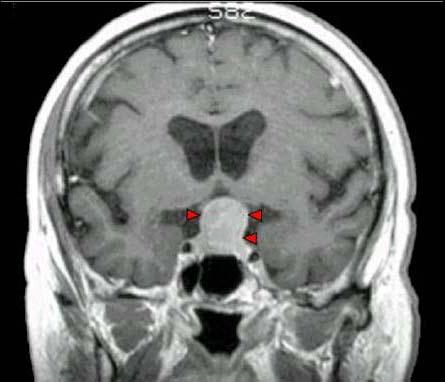

问题 男,37岁,视力模糊,部分视野缺失,伴有头痛、恶心数月,MRI检查如图,最可能的诊断为()

选项 A.颅咽管瘤 B.脑膜瘤 C.蛛网膜囊肿 D.垂体瘤 E.表皮样囊肿

答案 D